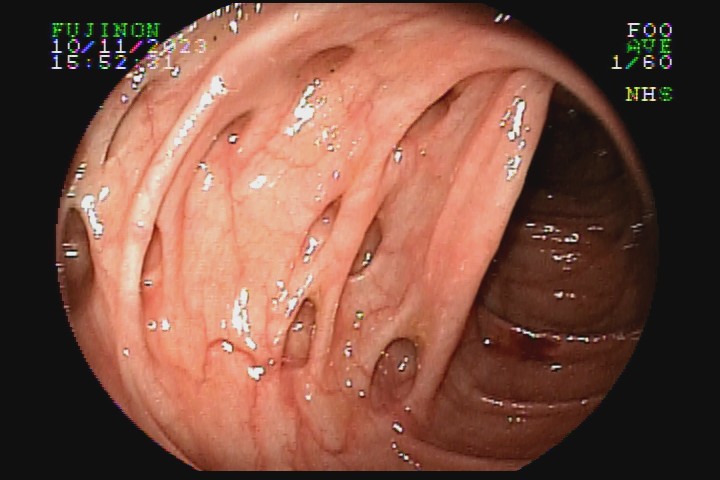

A diverticulose é uma doença adquirida, frequente entre pessoas mais idosas. Acredita-se que tenha como principal fator etiológico hábitos dietéticos relacionados com o refinamento da dieta industrializada. Pode ter uma evolução benigna por toda a vida e ser totalmente assintomática, mas pode também caracterizar-se como doença de sinais e sintomas agressivvos, com considerável morbidade e mortalidade devido às suas principais complicações: inflamação e sangramento.

A diverticulose cólica é consequência da herniação da mucosa do intestino grosso por entre as fibras musculares da parede intestinal. A diverticulose do cólon esquerdo complica mais com inflamação, e a diverticulose do cólon direito complica mais com sangramento.